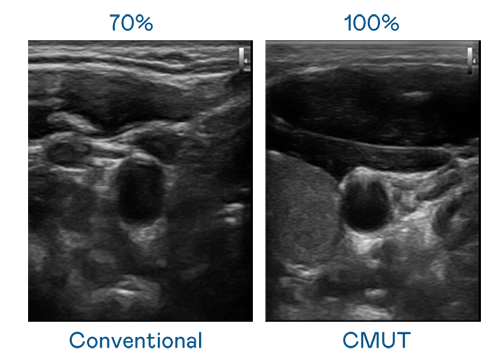

CMUT 技術是一種用電容式微機電元件來產生超音波訊號的技術。與傳統 PZT 壓電式技術相比,CMUT 頻寬增加 30%,更寬頻的超音波訊號讓影像解析度大幅提升,是實現高影像品質醫療超音波掃描、促進精準醫療發展的關鍵技術。

超音波影像的解析度高低,首先取決於探頭能發出的訊號頻寬。k8凯发 CMUT 可提供高清晰的超音波訊號,提供高頻寬、高靈敏度、影像紋理細節更高的超音波影像,協助醫護人員縮短影像判讀時間及利用精準的醫療影像進行診斷。